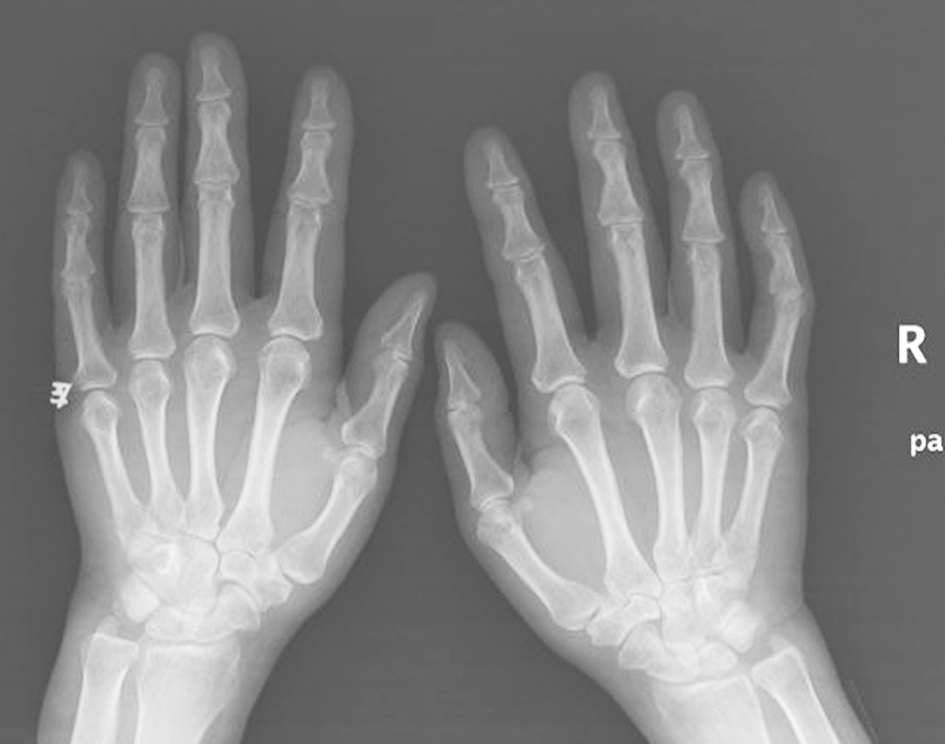

双手正位X线片:未见明显骨性异常(图7)。

图7双手正位X线片